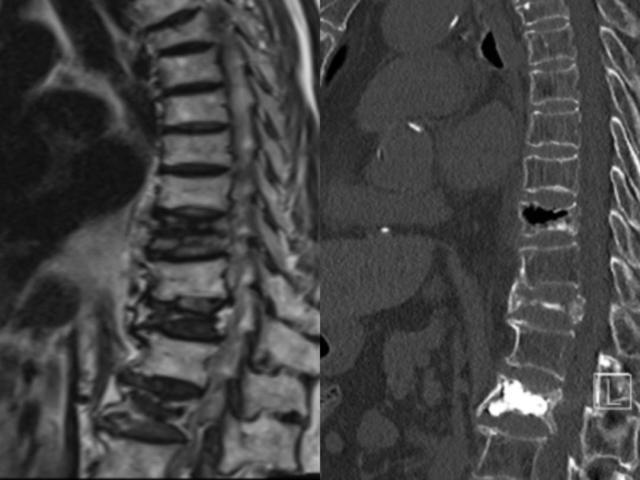

朱奶奶及家属十分不解,提出疑问:“为什么没有新鲜骨折,老人家会疼痛的这么厉害,甚至比去年发生腰3椎体新鲜骨折还痛苦,在床上动都动不了?”湖南省直中医医院脊柱外科汤毅副主任医师对此解释:“从核磁上看不明显,但是从CT上看,可以明确看到胸11椎体骨头是空的,医学上称之为“真空裂隙征”,陈旧性骨折没有愈合,椎体缺血坏死,即为Kummell病(陈旧性椎体骨折骨不连)。”

患者入院保守治疗效果欠佳,椎体压缩塌陷,汤毅副主任医师团队当机立断选择行胸11椎体骨折经皮球囊扩张成形术。术后疼痛缓解80%以上,患者起床翻身一点都不痛了,术后复查可见骨水泥弥散均匀。